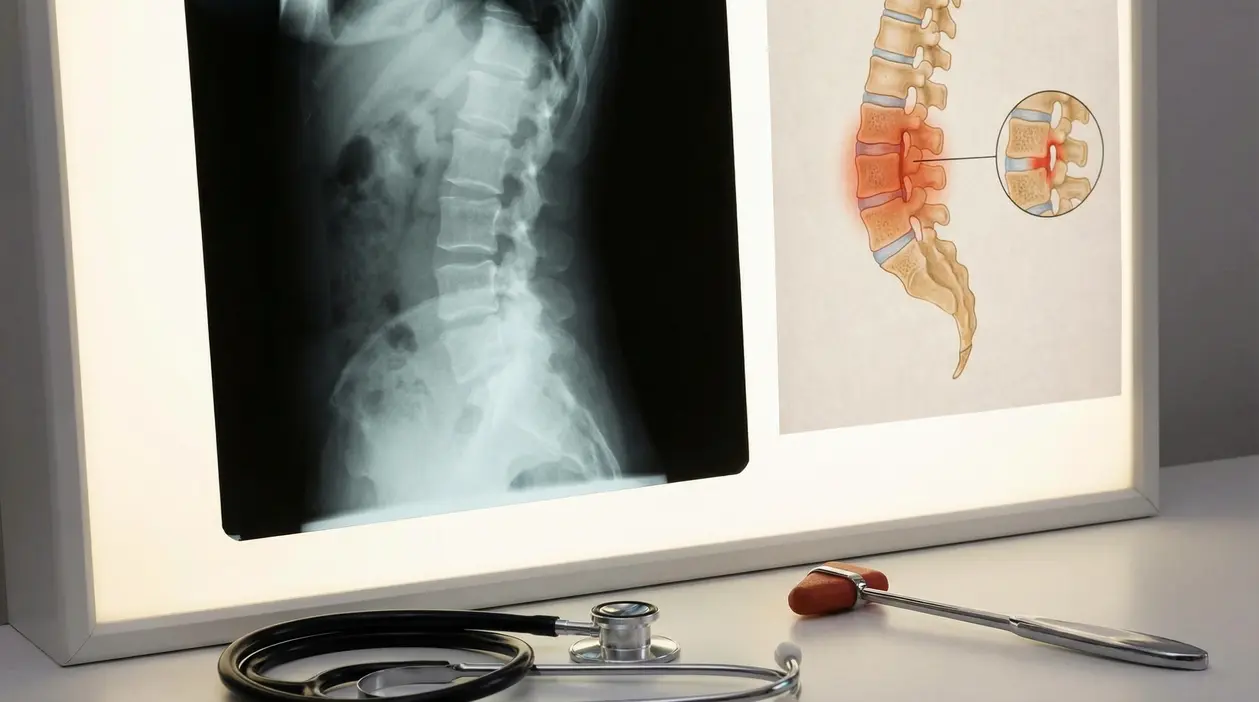

La spondiloartrite anchilosante è una malattia infiammatoria cronica che interessa soprattutto colonna vertebrale e articolazioni sacro iliache. Il problema non è solo il dolore: se trascurata, l’infiammazione può ridurre la mobilità e, nel tempo, favorire alterazioni strutturali.

- radiografie del bacino per cercare la sacroileite

- risonanza magnetica, utile anche nelle fasi iniziali